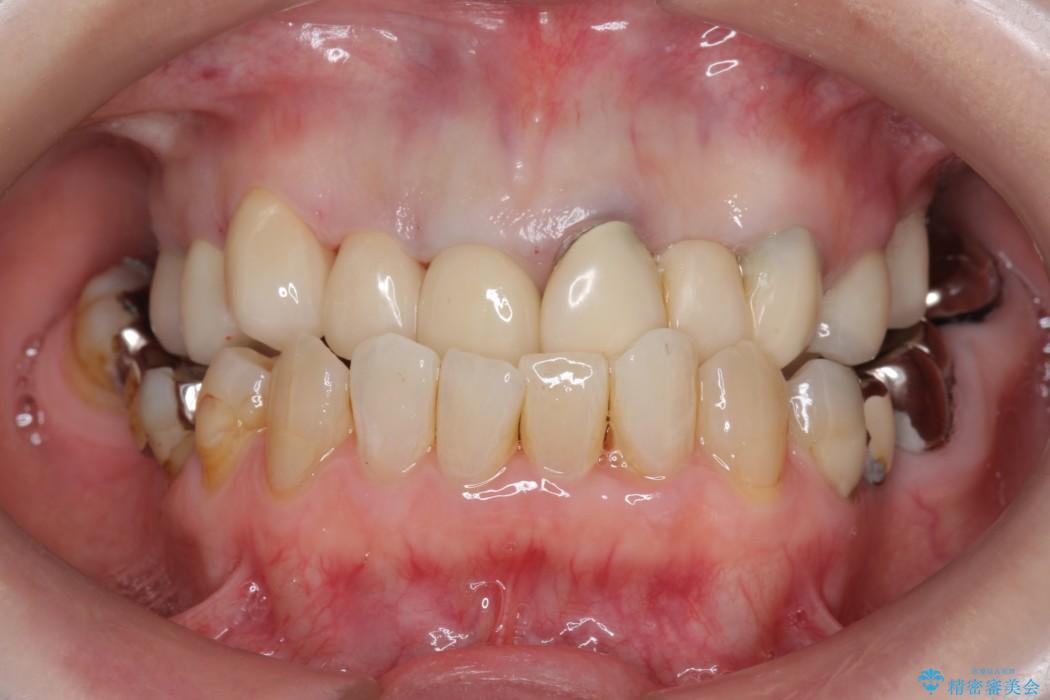

上顎右側の前歯2本のかぶせ物部分の再治療と犬歯に発生していた虫歯治療を主訴に来院されました。

前歯のかぶせ物に関しましては、内面が金属で覆われているため歯茎にその色が透けて見えるという審美的な問題と、かぶせ物と歯の境界が不適合であるという問題がありました。

犬歯の虫歯につきましては、何度も詰め物治療が繰り返されている痕跡があり今回虫歯を取りきるにあたり歯の強度に不安が残るため前歯と同時にかぶせ物の治療をしていくことを計画しました。